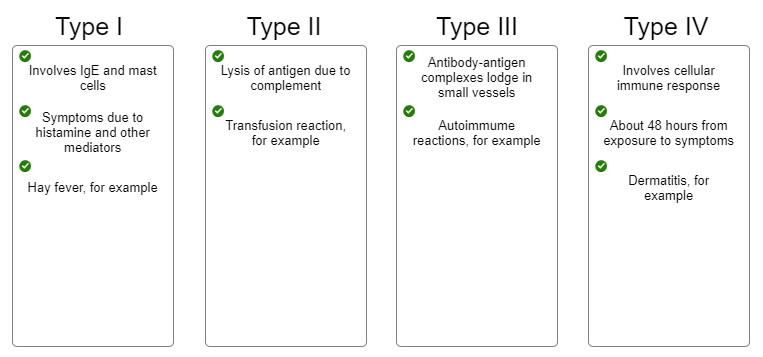

Indicate characteristic into the appropriate box, describing each type of hypersensitivity.

1. In antibody-dependent cytotoxic allergic reactions (type II), the

binding of __________ to targeted cells results in lysis of those

cells.

2. Which of the following transfusions would result in an

antibody-dependent cytotoxic (type II) allergic reaction?

1. Antibodies

2. Type A blood given to a type B recipient

1. Immune complexes that are not removed by macrophages can react

with and activate __________.

2. The degranulation of cells

called __________ occurs in response to the activation of complement

by immune complexes. The result is __________ of blood vessels. This

leads to some of the symptoms of a type III hypersensitivity

reaction.

3. 3. The presence of the immune complexes and

complement attracts and activates neutrophils, causing them to

degranulate. What is the effect of neutrophil activation? (This effect

will also lead to some of the symptoms of a type III response.)

1. Complement

2. Basophils; vasodilation

3. Tissue damage

1. Delayed hypersensitivity is __________ mediated.

2. What type

of cell is responsible for contact dermatitis and tissue

rejection?

3. In a reaction to poison oak or poison ivy, a small

molecule from the plant, called a(n) __________, will bind to a host

molecule, triggering an allergic reaction.

4. What is presented

on the macrophage surface?

5. First exposure to the allergen

(hapten) causes an increase in the number of __________.

6. What

attracts additional macrophages and causes their release of mediators

of inflammation?

1. Cell

2. Th1 cells

3. Hapten

4. Hapten plus class II

MHC

5. Th1 cells

6. Release of cytokines from Th1 cells